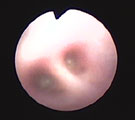

初診時。膿性鼻汁と湿咳あり。重度の肺機能低下 胸部レントゲン。左右の肺野後部に淡い浸潤影。 気管支鏡所見。左後葉気管支内に粘稠分泌物 治療開始2ヶ月後。肺機能は正常化し元気になった。

経過:受診時、膿性鼻汁と湿咳ありやや呼吸困難を示した。血液検査ではリンパ球増加ありジステンパーを肯定できなかった。胸部レントゲンでは左右の肺野後部に淡い浸潤影がみられた。動脈血酸素分圧は著しく低下し(PaO2 58.2 mm Hg)、重度の肺機能低下を示した。肺感染症が疑われその病原体診断のため気管支鏡検査を行った。気道粘膜全体にわたり浮腫著明であった。LB2,LB2D1,LB2V1,LB2V2, LB2D2入口部より粘稠分泌物が湧き出てきた。BAL(LB2V1)の回収率は9%ときわめて低かったが、総細胞数が4405 /μLと著しく増加しその91.5%は好中球であった。典型的な急性好中球性炎症パターンであった。また回収液からBordetella bronchiseptica が1.0×10CFU/ml検出され、ABPC, AMPC, CFPM, GM, AMK, MINO, OFLX, ENXに感受性、CEZ, CEX, CLDMに耐性を示した。下気道感染症(LRTI)と診断した。抗生剤と去痰剤投与を開始した。2ヶ月後には鼻汁と咳が完全に消失しPaO2 96.6 mm Hgと肺機能も正常化した。